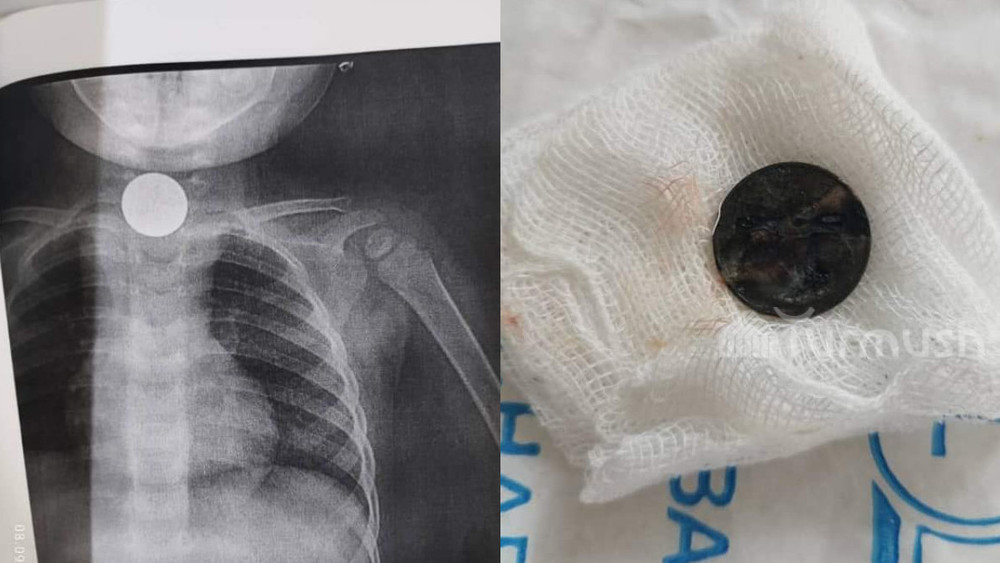

Сторонний предмет 2 месяца находился в ребенке: В Оше провели сложную операцию (фото)